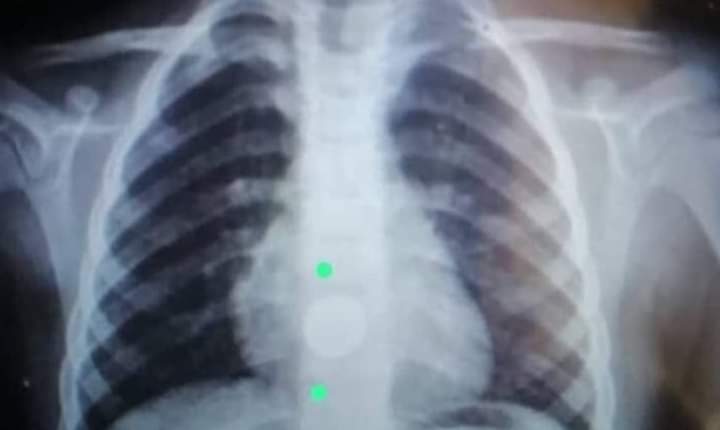

استطاع الأطباء في مشفى حماة الوطني في سوريا من سحب بطارية على شكل قرص من مريء طفل عمره 5 سنوات بعد 6 أيام من ابتلاعها.

وقال المدير العام للهيئة العامة لمشفى حماة الوطني الدكتور سليم خلوف إن طفلا بعمر 5 سنوات وصل إلى الشعبة الهضمية بعد 6 أيام من ابتلاعه بطارية على شكل قرص.

وأضاف سليم خلوف أنه تم إجراء تنظير هضمي علوي كشف أن البطارية كانت محشورة بالمريء وتم سحبها بملقط خاص بالأجسام الغريبة.

وأوضح أنه تمت إعادة التقييم للمكان تنظيريا حيث لوحظ تقرح واسع مع نزف في المخاطية مكان الانحشار.